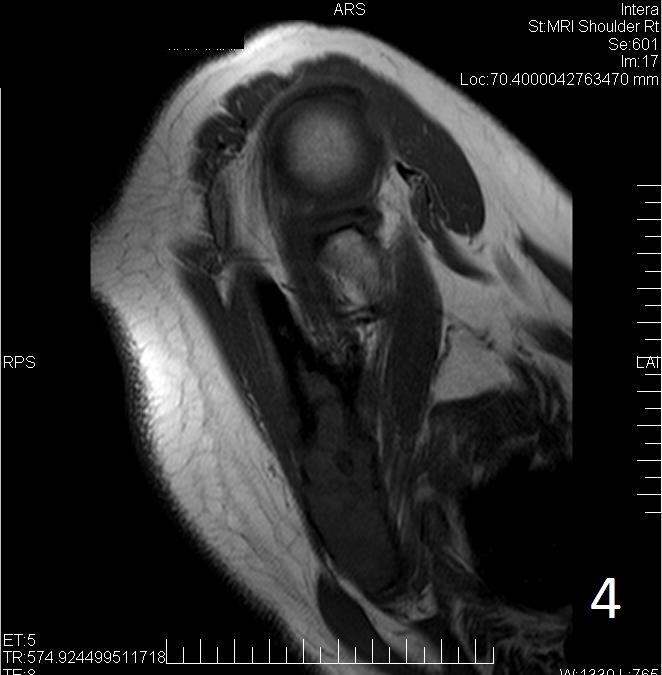

• MRI can have a very variable appearance and enhancement pattern; May not follow same signal as fibrous tissue which is normally Low signal on T1 and T2

• Low-intermediate heterogenous signal on T1 (Fig. 4)

Fig. 4. Axial T1W of fibrous dysplasia of the scapula shows a lesion with similar signal intensity as muscle.